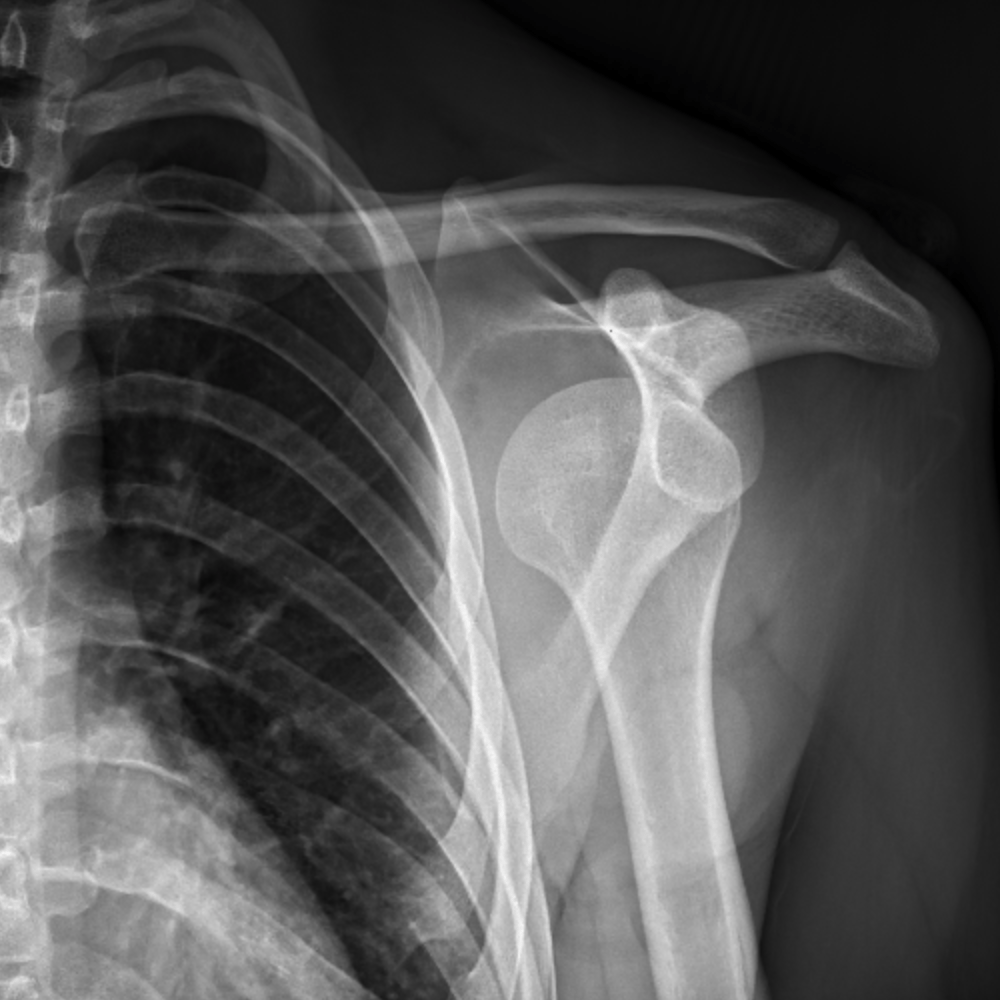

Hill-Sachs lesion with bony Bankart lesion | Image ...

Hill-Sachs lesion with bony Bankart lesion | Image ... from images.radiopaedia.org